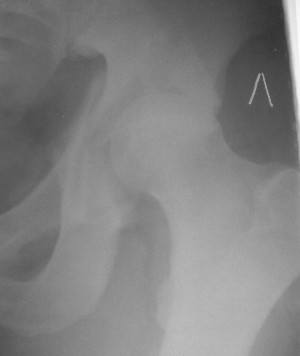

Больной 18 мая 2003 года в автоаварии получил перелом левой вертлужной впадины, вывих бедра. Госпитализирован в один из стационаров области.Вывих вправлен. В последствии бедро вывихивалось еще дважды. На консультацию был представлен снимок от 19.05.03г., больной переведен к нам 3.06.03г. Снимок при поступлении - перелом впадины, задне-верхний вывих бедра. 05.06.2003 г. выполнено открытое вправление вывиха левого бедра и остеосинтез стенки вертлужной впадины двумя винтами. Послеоперационный период без осложнений. Объем движений в левом тазобедренном суставе восстановился полностью. Выписан на амбулаторное лечение в удовлетворительном состоянии с рекомендациями 3 месяца ходить на костылях без нагрузки на оперированную конечность. На контрольных рентгенограммах левого тазобедренного сустава 13.10.2003 г. - признаки консолидации перелома; плотность, форма головки и состояние суставных поверхностей удовлетворительные. Разрешена дозированная осевая нагрузка, на конечность с использованием дополнительной опоры. 19.12.2003 г. больной обратился с жалобами на боли в левом тазобедренном суставе. На рентгенограммах левого тазобедренного сустава 19.12.2003 г., 20.02.04г. - асептичекий некроз головки бедра. 5.04.04г. - эндопротез. Сейчас ходит без трости, не хромает. Особенность эндопротезирования - при удалении винтов прослежена линия перелома заднего края впадины и предложено установить чашку несколько меньшего диаметра, чтобы она была покрыта несломанной частью.